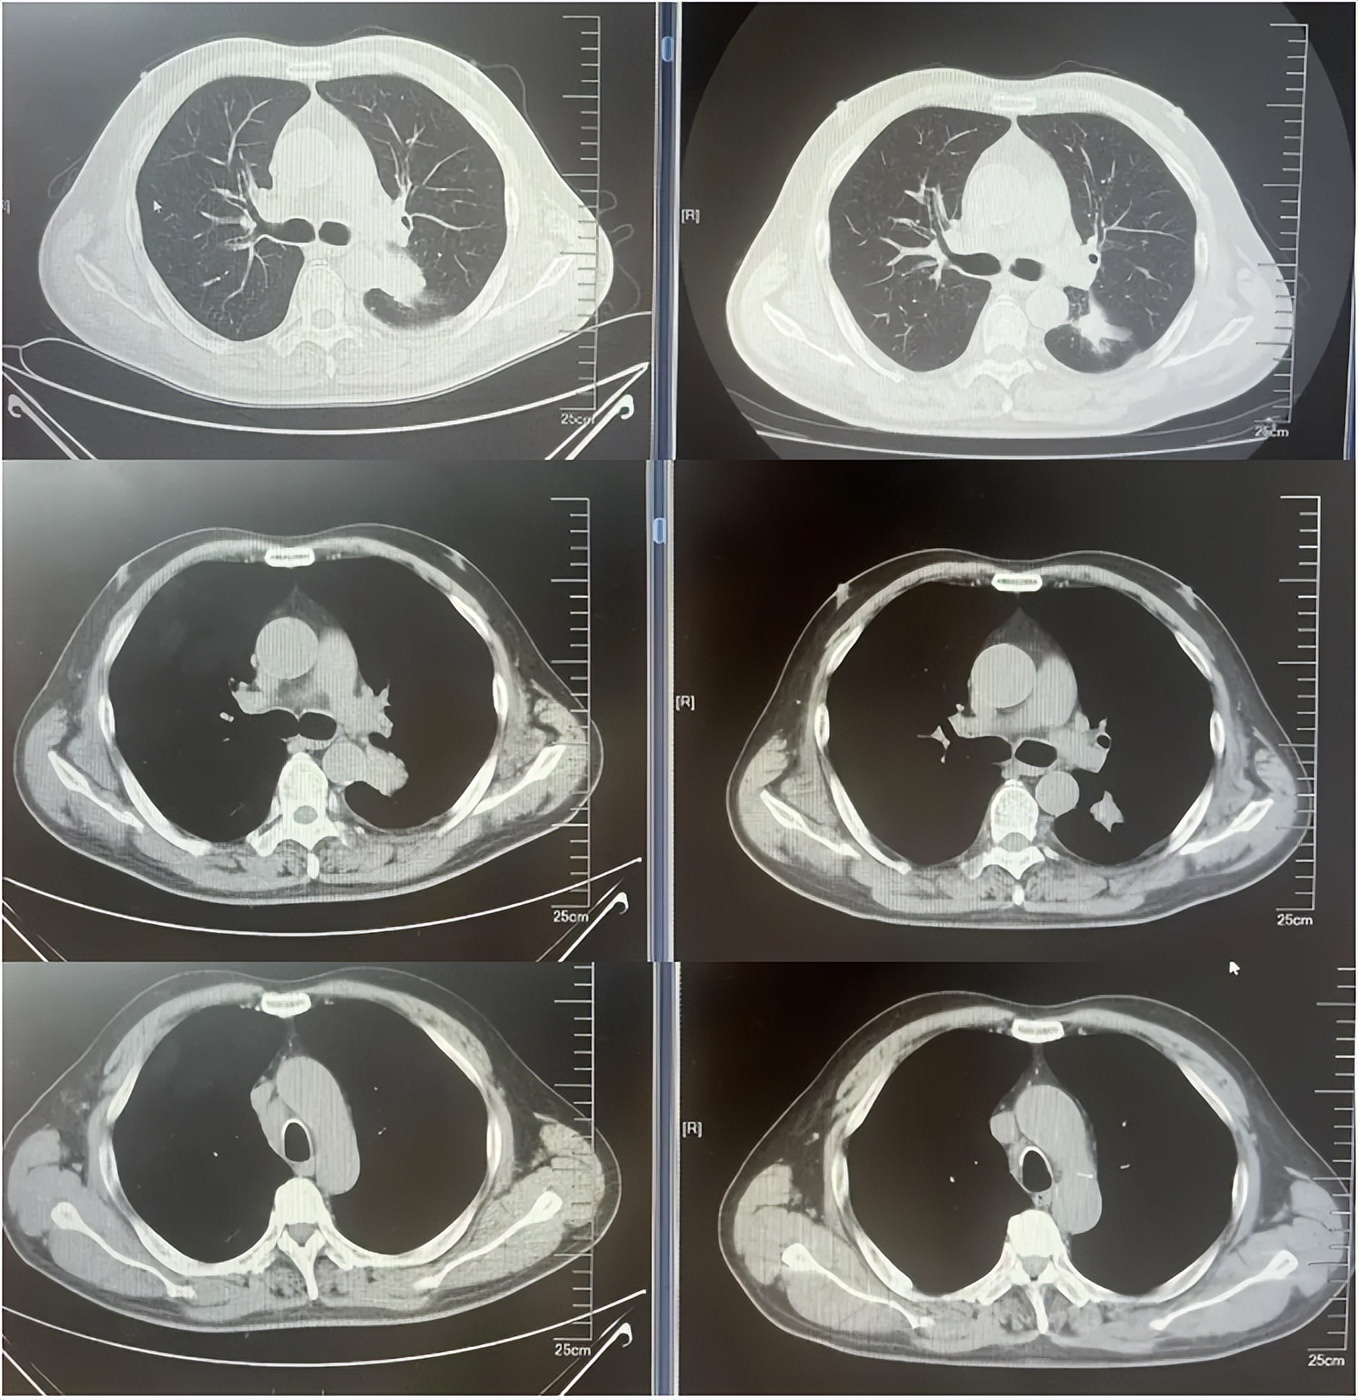

病例2:患者男,61岁。2023年8月于外院行肺CT提示:右肺下叶肿块。2023年10月23日于我院行单孔胸腔镜下右肺下叶切除术、肺门纵隔淋巴结扩清术。术后病理:腺癌低分化(腺泡型占30%,乳头型占30%,筛状占30%,微乳头占10%)。分期pT4N0M0 IIIA期。术后行基因检测提示HER2+(14%),PD-L1 2%+。术后行AC方案化疗4周期后行阿替利珠单抗维持治疗1年。末次用药时间:2024年11月1日。2025年2月复查肿瘤标志物升高,肺HRCT示:双肺多发结节,考虑转移。行血液基因检测提示:ERBB2 35.5%突变,CDK1 9.5%突变,MDM2 4.92%突变。患者DFS 14m,阿替利珠单抗停药后3个月出现复发转移,可见传统免疫治疗效果不佳。恰逢德曲妥珠单抗一线新尝试DESTINY-lung 04研究公布了入组标准和治疗方案,且该患在术后的组织基因检测和复发后的血液基因检测中都明确存在HER2突变,故行德曲妥珠单抗一线治疗。最佳疗效PR,目前治疗持续有效,PFS超过6个月。无药物相关不良反应发生。

德曲妥珠单抗治疗4周期(2025.4)疗效对比